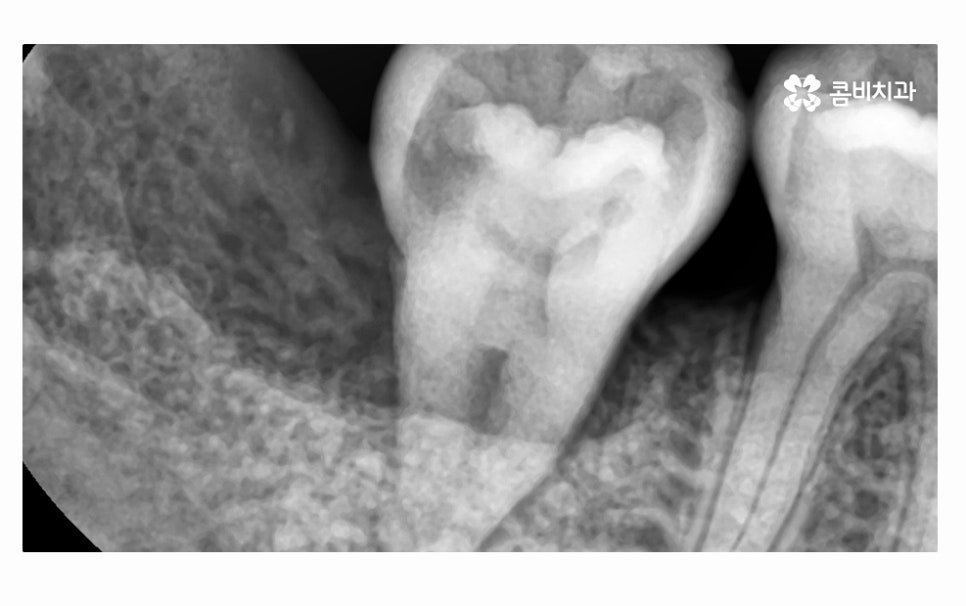

오늘 소개드릴 환자분의 케이스는 치아 상실의 요인이

잇몸질환이 심해져서 치아 뿌리까지 염증이 발생되었고

결국 어금니 발치 까지 이어진 사례라고 할 수 있는데요.

어금니 발치까지 이어지도록 청결 관리에 악영향을 준 요소로는

평소의 식습관이나 칫솔질 부분도 컸겠지만

불규칙한 치열과 옆으로 누운 사랑니도 영향이 컸으며